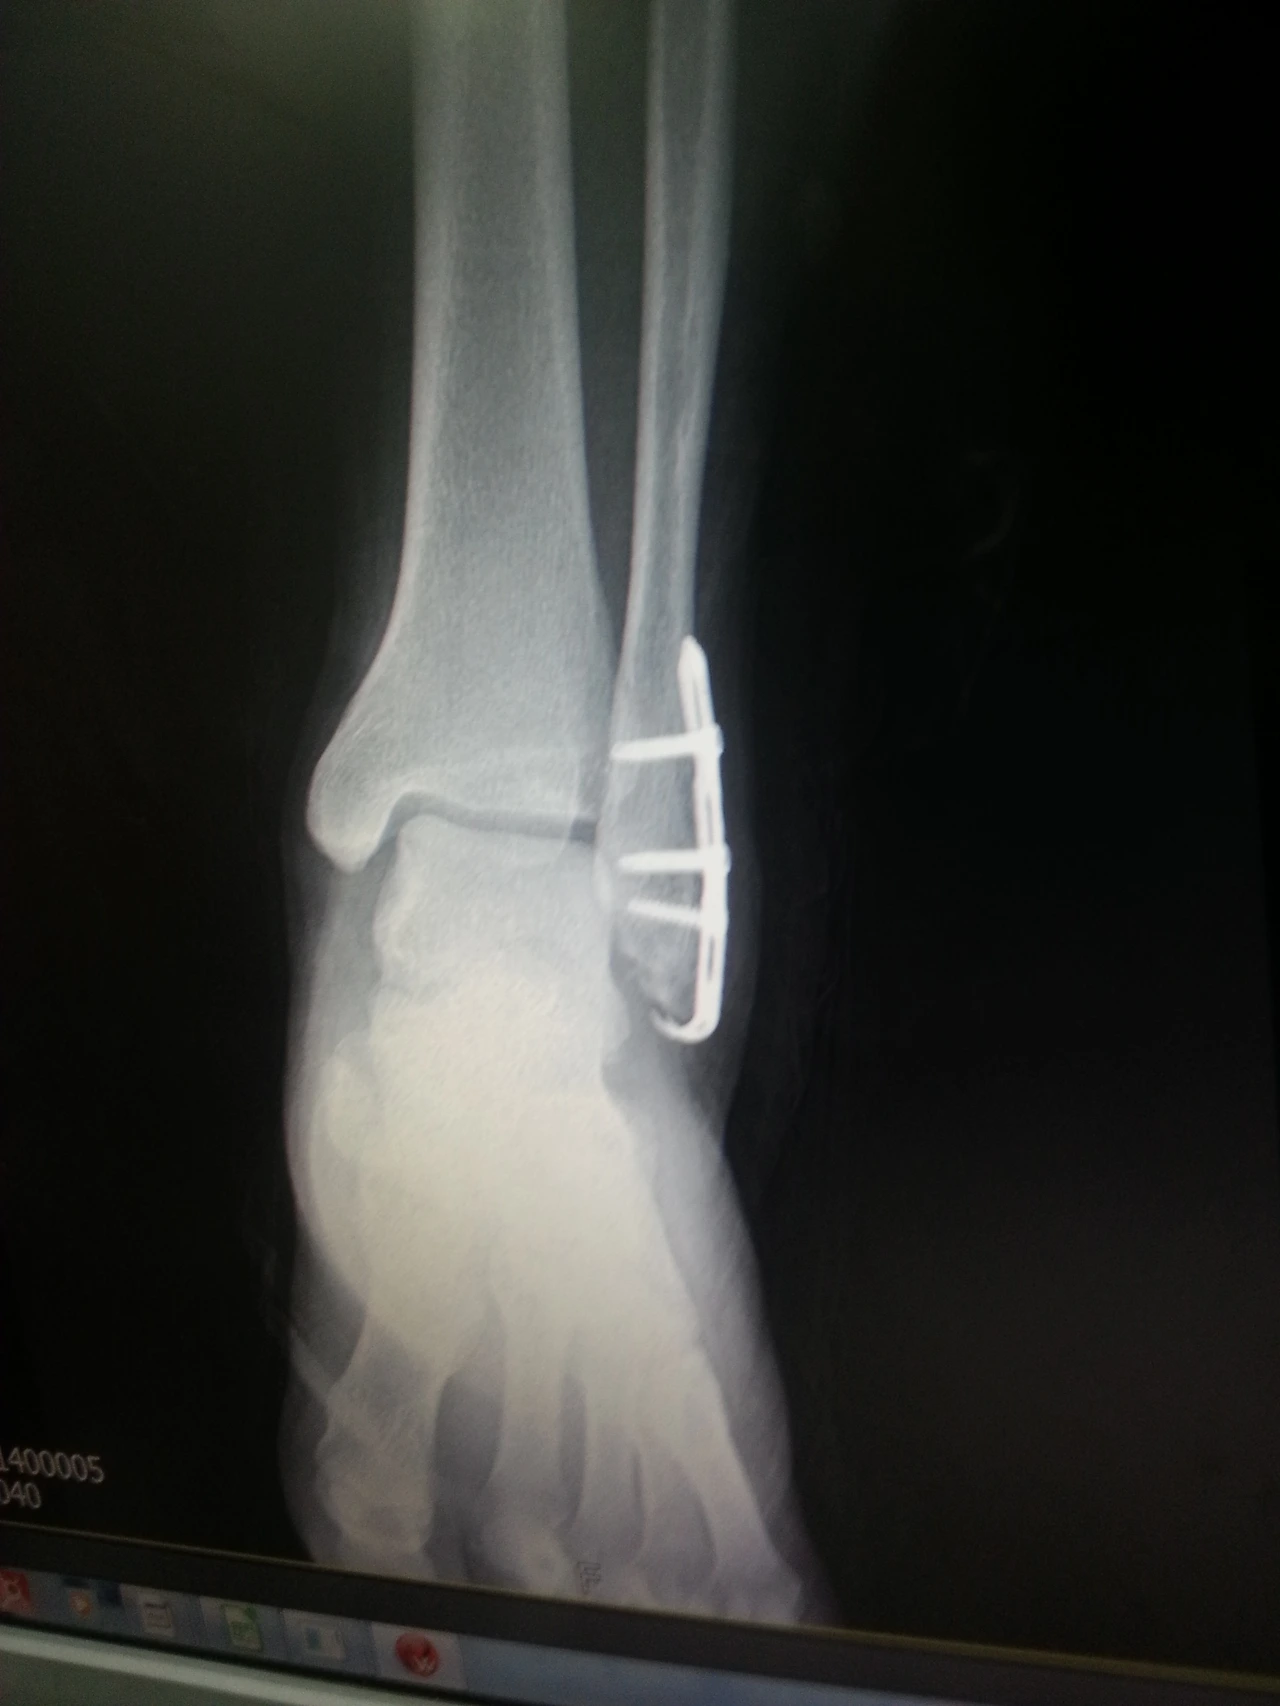

2015년 10월 7일 오후 5시 배구 경기 도중 발목 골절로 인한 입원

수술한 내 발목.